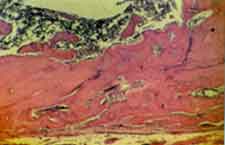

Grupo I (implante). Em todos os espécimes, o implante encontra-se na íntegra no interior da loja cirúrgica sem evidências de reabsorção. Em contato com o material, observa-se delgada faixa de tecido conjuntivo neoformado (Figura 1 ). Logo a seguir, notam-se trabéculas ósseas neoformadas delgadas que exibem amplo espaço inter-trabecular e elevado número de osteoblastos em suas bordas (Figura 1 ). Em alguns casos evidencia-se formação de tecido em íntimo contato com o implante.

Figura 1